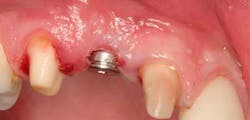

Immediately post-insertion, a periapical radiolucency was detected on the post-insertion radiograph on tooth No. 7 and the patient was immediately sent for root canal therapy. Four months was allowed for implant integration. At the time of Stage II, a noninvasive punch tissue technique was employed and a 3 mm healing abutment was placed. At the time of impression, an open tray technique was used and a custom abutment was selected. Because of the patient’s canine guidance occlusion, a porcelain-fused-to-metal crown was selected along with all-ceramic crowns on teeth Nos. 5 and 7.